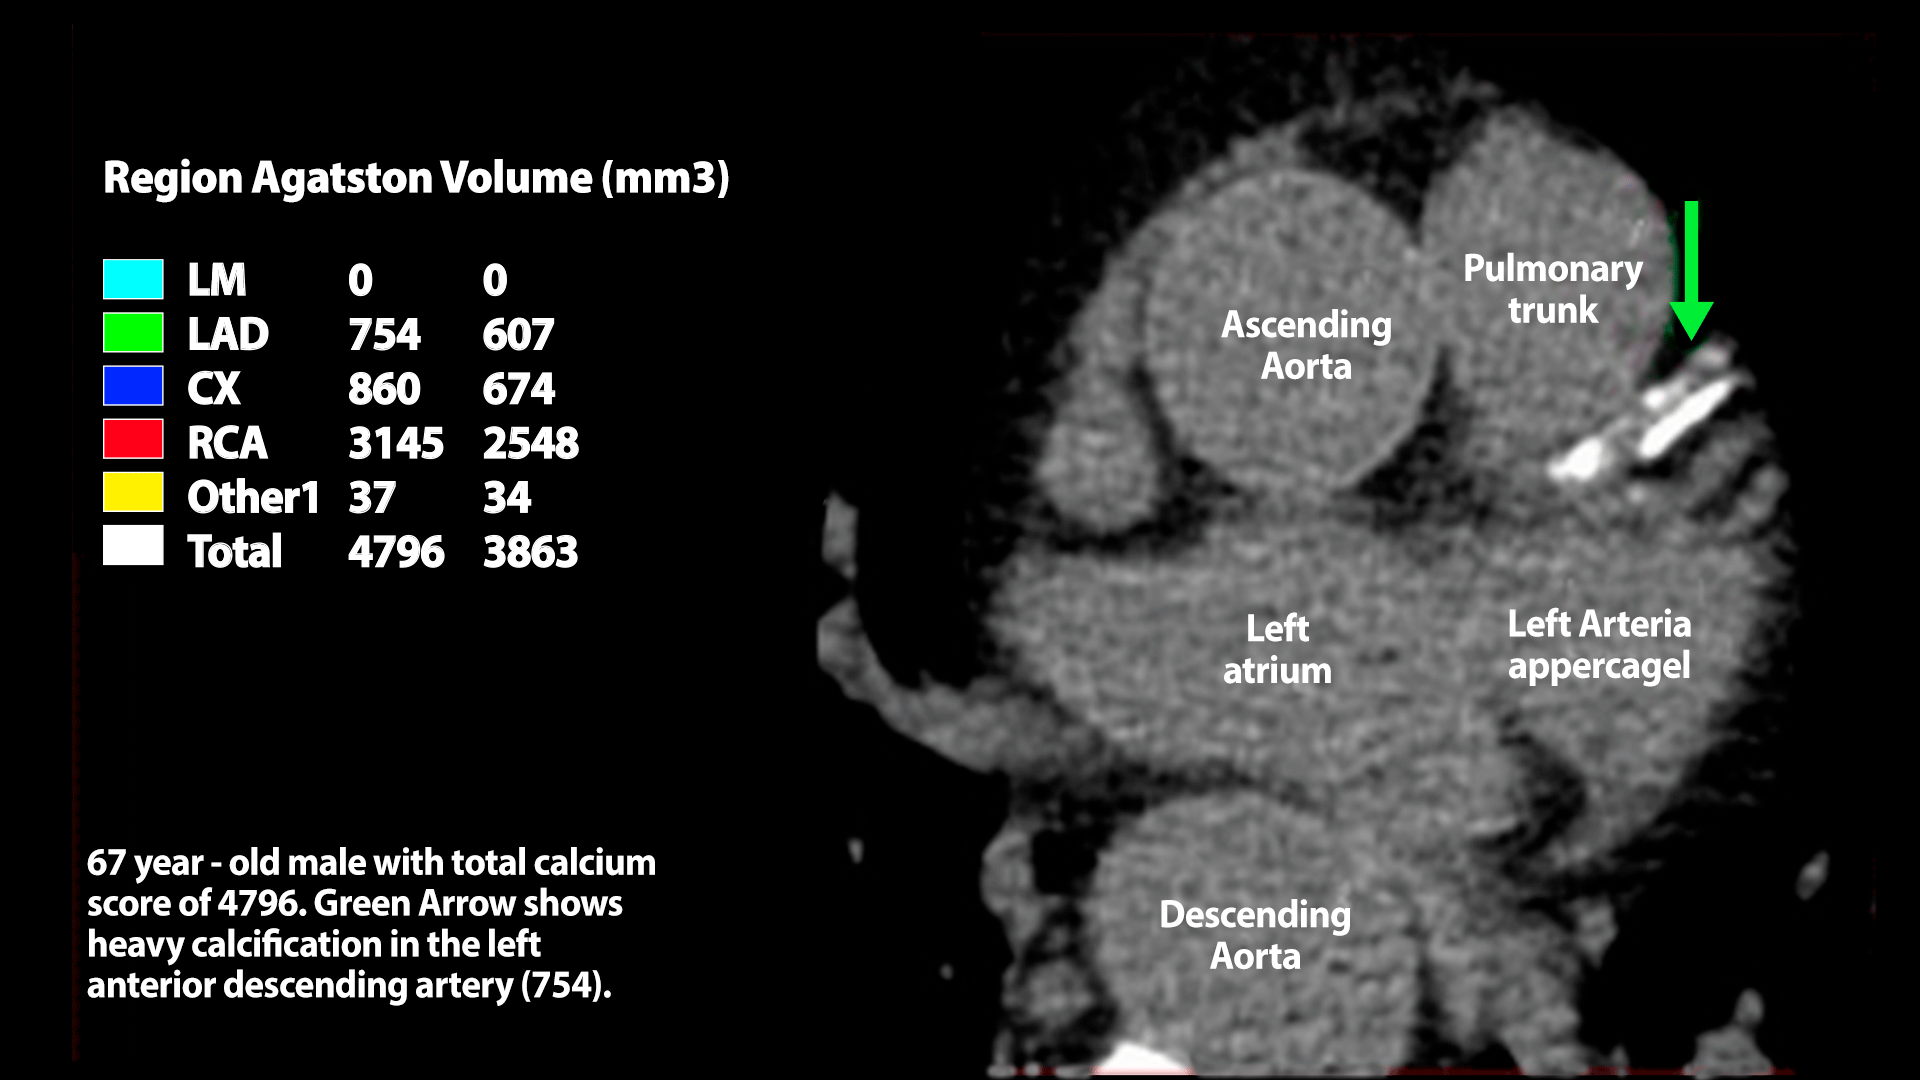

Your heart’s “calcium score” predicts risk better than stress tests or angiograms

A coronary calcium (CAC) score of zero means very low risk—but once it rises above 100, statins are recommended. A score over 300 signals a danger level equal to someone who’s already had a heart attack, stroke, or bypass surgery. When combined with other risk factors, CAC scoring becomes a powerful tool to predict—and prevent—future heart attacks. (Chapter 2)